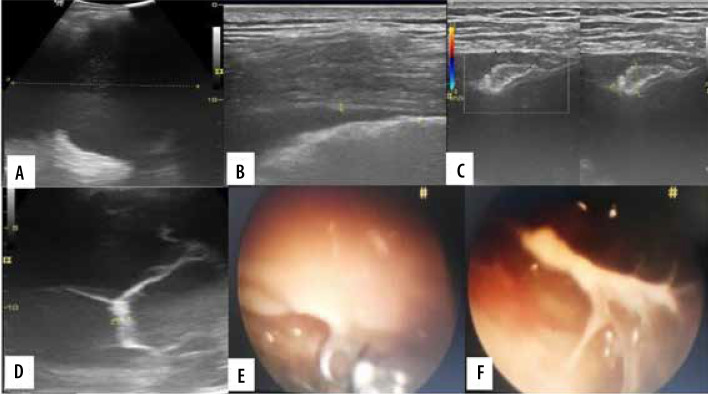

Purpose: The purpose of this study was to evaluate the use of the transthoracic ultrasonography (US) for pleural adhesions and pleural thickening and to quantify pleural effusion by standardised sonographic techniques and its comparison with thoracoscopic findings. An assessment of the association between pleural thickness and pleural nodularity with histopathological examination findings was also attempted.

Material and methods: Thirty-one patients with suspected chest pathologies were initially assessed by transthoracic US followed by videothoracospy. Findings observed were noted and appropriately analysed statistically.

Results: Transthoracic US is 100% sensitive and specific for detecting pleural septations in the presence of pleural effusion with 100% accuracy. Gliding sign is a highly sensitive and specific sign to detect the pleural septations in absence of pleural effusion. There was no significant association of thickness of pleural septation with the pleural malignancy.

Conclusions: Transthoracic US plays an important role in the quantification of pleural effusion, assessment of the pleura and pleural space for pleural adhesion, pleural thickening, and guiding trocar insertion.